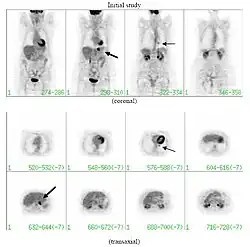

PET scan

If there is an intermediate risk of malignancy, further imaging with positron emission tomography (PET scan) is appropriate (if available). It can be done simultaneously as a CT scan in the form of PET-CT. Around 95% of patients with a malignant nodule will have an abnormal PET scan, while around 78% of patients with a benign nodule will look normal on PET (this is the test sensitivity and specificity).[15] Thus, an abnormal PET scan will reliably pick up cancer, but several other types of nodules (inflammatory or infectious, for example) will also show up on a PET scan. If the nodule has a diameter of less than one centimeter, PET scans are often avoided because of an increased risk of falsely normal results.[15][16][17] Cancerous lesions usually have a high metabolism on PET, as demonstrated by their high uptake of FDG (a radioactive sugar).

-

PET-CT of a tuberculoma.